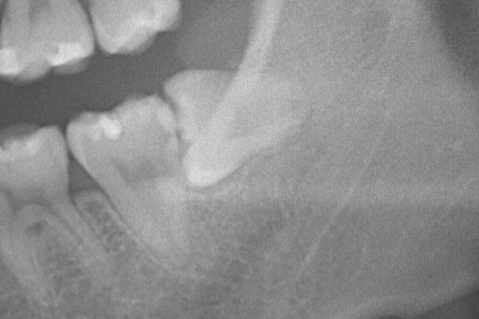

歯茎の下にほぼ全て埋まった親知らずの抜歯